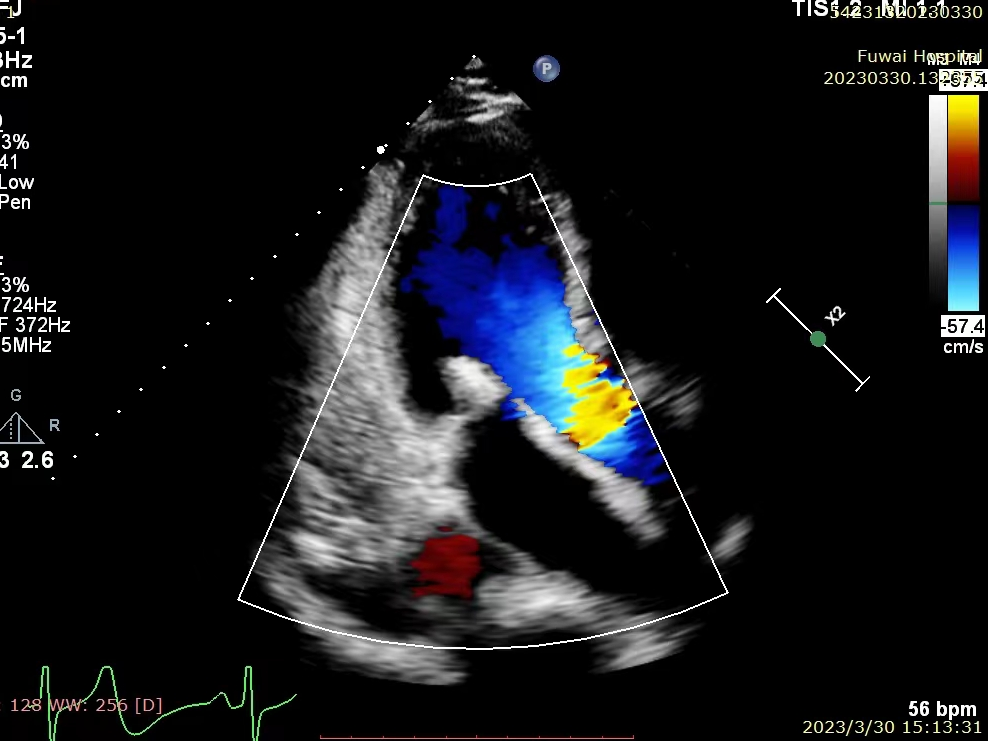

患者术前超声

患者为高龄男性,年龄82岁。术前超声心动图诊断为重度退行性二尖瓣反流(MR 4+),反流位于2区,后叶P2区脱垂合并腱索断裂,多普勒检查可见大量偏心性反流。心脏团队评估该患者为外科高风险患者,考虑使用MitraClip™进行经导管二尖瓣缘对缘治疗,因患者有食道狭窄病史,经术前讨论评估,决定为该患者行单纯经胸超声(TTE)引导下MitraClip™手术。